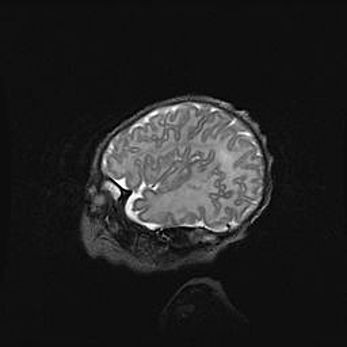

Церебральная ишемия II.

Возраст: 5 дней

Вес: 3400 г

Пол: женский

Окружность головы: 35 см

Срок гестации: 39 недель

Церебральная ишемия – это заболевание, характеризующееся недостаточностью (гипоксией) либо полным прекращением (аноксией) снабжения мозга кислородом по причине закупорки одного или нескольких сосудов. Это приводит к  что метаболическим расстройствам различной степени тяжести в тканях головного мозга, развитию коагуляционных некрозов и гибели нейронов.